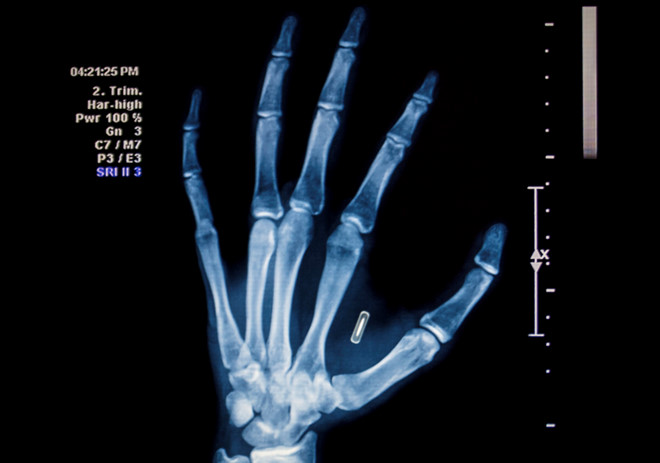

22/11/2018 16:10Cấy chip vào người sống - trào lưu đang nổi lên toàn cầu

Một số hãng luật và tài chính của Anh đang đàm phán với công ty sản xuất chip điện tử để cấy ghép các microchip RFID cho nhân viên nhằm mục đích an ninh.

Việc cấy ghép chip cho nhân viên cũng không phải quá mới mẻ. Năm 2017, công ty Three Square Market ở Wiconsin, Mỹ đã cấy ghép chip cho hơn 80 nhân viên. Các chip RFID nhỏ bằng kích cỡ hạt gạo được cấy vào tay để nhận diện, cho phép nhân viên vận hành máy móc đúng trách nhiệm của mình. Thú vị ở chỗ, Three Square bán máy bán hàng tự động nhưng đồng thời cũng là nhà gia công cấy ghép chip.

Năm 2006, City Watcher trở thành công ty đầu tiên của Mỹ cấy ghép chip theo dõi công nhân. Họ yêu cầu toàn bộ nhân sự làm việc ở trung tâm dữ liệu phải được cấy ghép RFID vào cơ tam đầu ở cánh tay. Tuy nhiên đến năm 2007, bang California lại cấm các công ty buộc nhân viên phải cấy ghép RFID, cũng như đối với sinh viên trong tiểu bang.

Trào lưu gắn chip cho nhân viên Mỹ, Anh hiện nay thực tế xuất phát từ Thụy Điển. Theo LA Times, từ tháng 1/2015, Vườn ươm trung tâm thủ đô Stockholm với khoảng 100 công ty và 2000 nhân viên đã bắt đầu thực hiện. Đến nay, đã có khoảng 150 công nhân được cấy ghép.